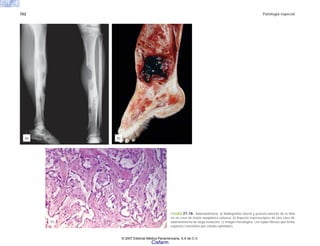

Hígado

Vesícula biliar

Páncreas

Retroperitoneo

Ganglios linfáticos